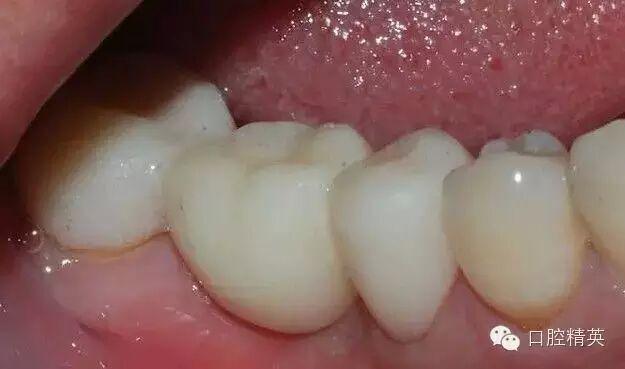

鄰面制備完成后

修整后

排齦后,制備肩臺